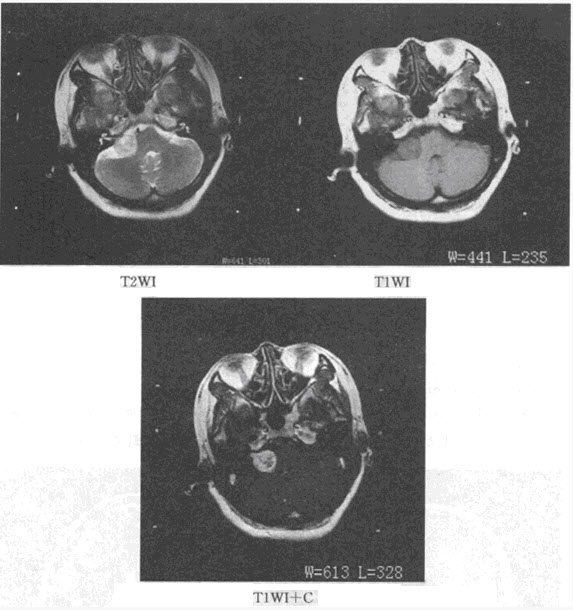

患者,男,56岁。因背部疼痛2个月入院;查体:胸椎T~T棘突和椎旁有压痛,胸椎活动受限。体温38.4℃,X线平片和CT见下图。

(单选题)首先考虑为何种疾病()

(多选题)下列哪几项支持诊断()